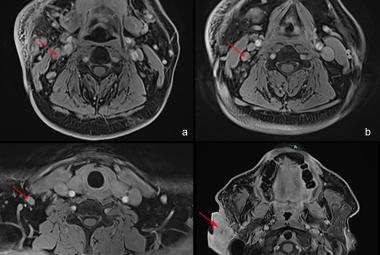

Temporal ependymomas are exceedingly rare intracranial neoplasms originating from ependymal cells within the temporal lobe. The rare nature of these tumours makes diagnosis and treatment extremely difficult in the field of neuro-oncology. These tumours frequently encounter misdiagnosis as meningiomas or other extra-axial lesions due to their atypical location and the absence of distinctive features. Consequently, histopathological examination becomes essential for accurate evaluation and a precise diagnosis. This article presented a unique case of a 25-year-old male patient’s supratentorial ependymoma at the temporal region. The report described the patient’s clinical presentation, including progressive headaches, abnormal behaviour and vomiting, leading to timely diagnostic investigations. After a surgical resection, the diagnosis of ependymoma was confirmed by histopathological analysis. Following surgery, the patient defaulted follow-up and presented six months later with worsening symptoms. Radiological imaging proved the tumour’s significant growth. The second resection worsened his neurological deficits. Unfortunately, adjuvant radiotherapy would not be beneficial to him at this point. He received palliative care. The case study emphasises the difficulty in diagnosing and treating temporal ependymomas, underscoring the importance of multidisciplinary collaboration and evidence-based approaches for optimal patient outcomes.